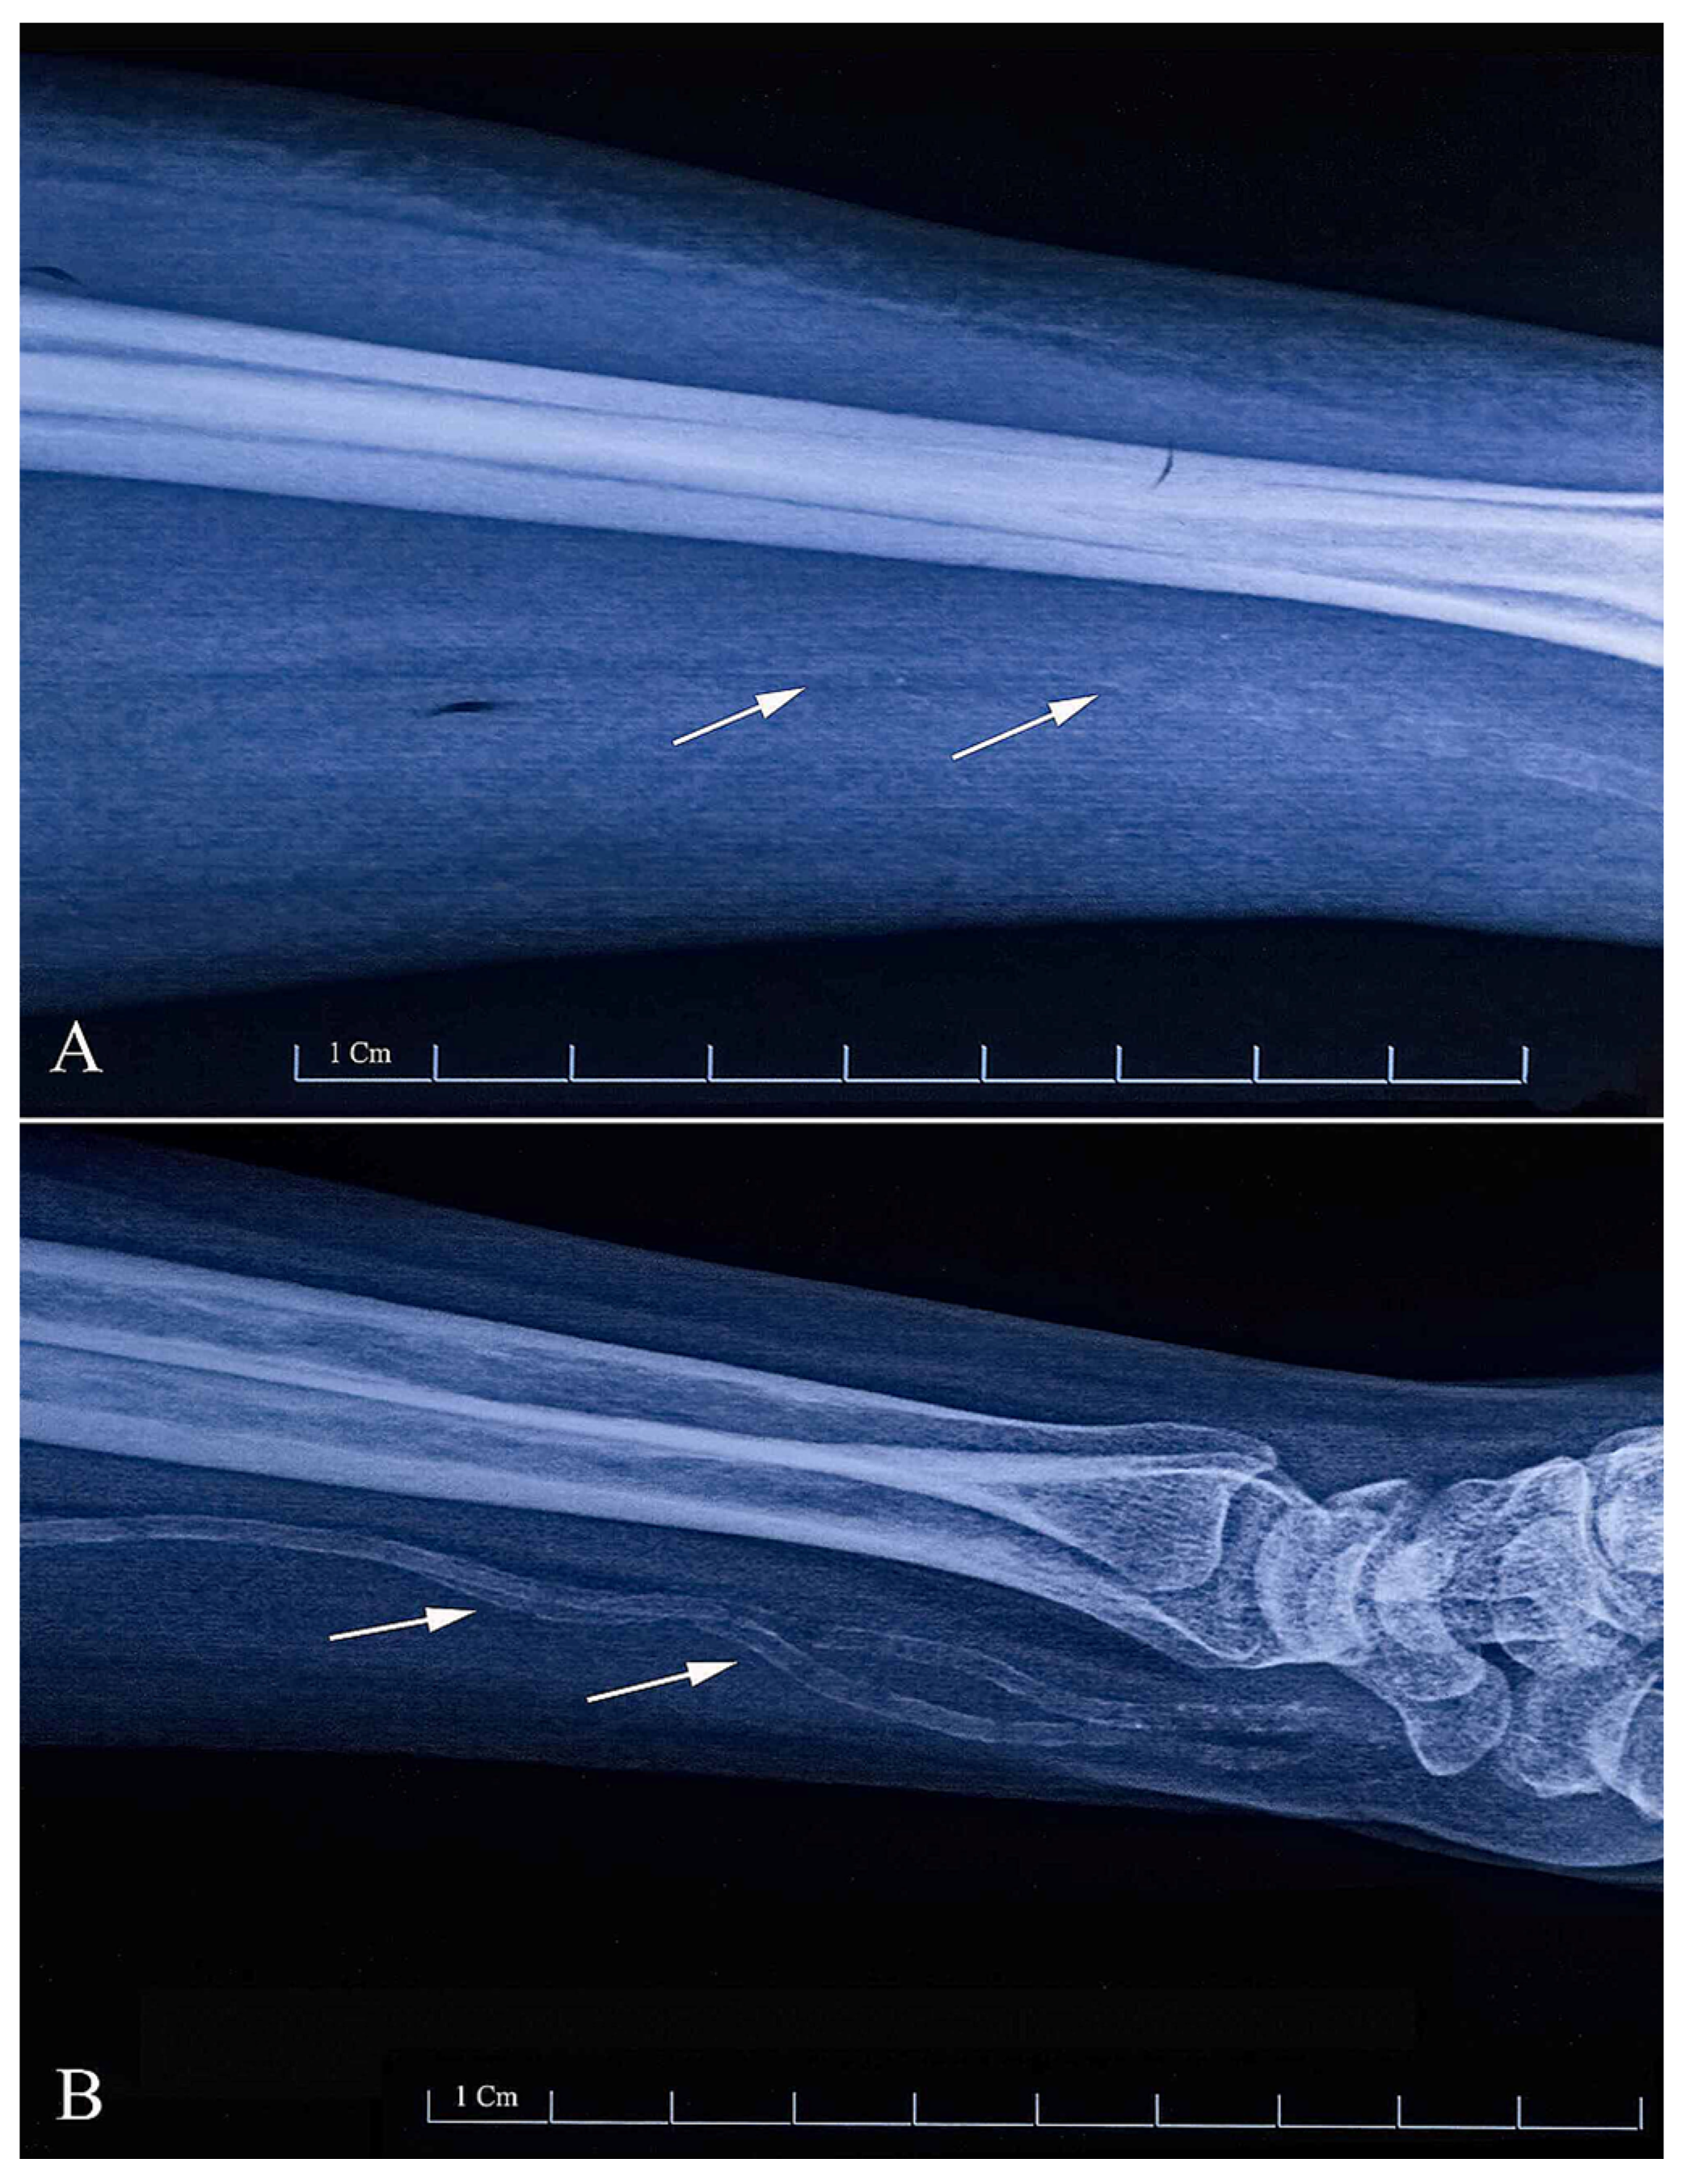

4.1.2. Plain Radiograph

4.1.3. B-Mode Ultrasound